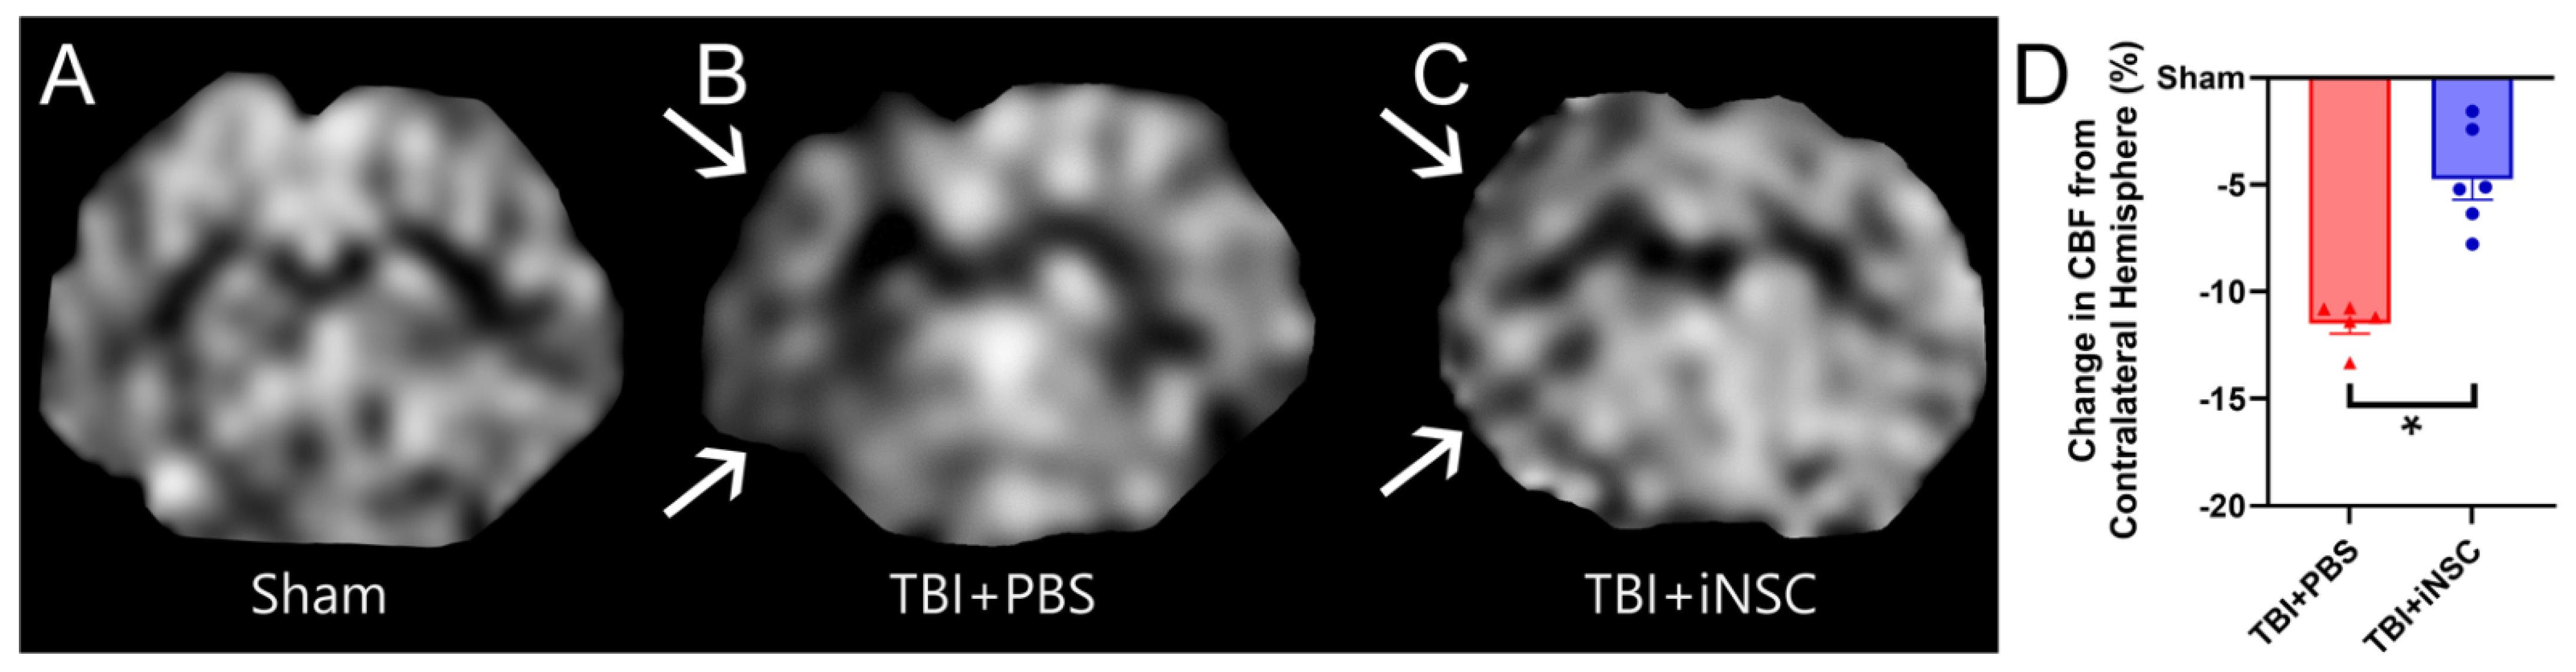

3.4. iNSC Transplantation Significantly Decreased Ipsilateral Atrophy, Lesion Volume, and Midline Shift While Preserving Cerebral Blood Flow

- O’Brien, N.F.; Maa, T.; Moore-Clingenpeel, M.; Rosenberg, N.; Yeates, K.O. Relationships between cerebral flow velocities and neurodevelopmental outcomes in children with moderate to severe traumatic brain injury. Child’s Nerv. Syst. 2018, 34, 663–672. [Google Scholar] [CrossRef]

- Barlow, K.M.; Iyer, K.; Yan, T.; Scurfield, A.; Carlson, H.; Wang, Y. Cerebral Blood Flow Predicts Recovery in Children with Persistent Post-Concussion Symptoms after Mild Traumatic Brain Injury. J. Neurotrauma 2021, 38, 2275–2283. [Google Scholar] [CrossRef]

- Gsell, W.; De Sadeleer, C.; Marchalant, Y.; MacKenzie, E.T.; Schumann, P.; Dauphin, F. The use of cerebral blood flow as an index of neuronal activity in functional neuroimaging: Experimental and pathophysiological considerations. J. Chem. Neuroanat. 2000, 20, 215–224. [Google Scholar] [CrossRef]

- Ware, J.B.; Dolui, S.; Duda, J.; Gaggi, N.; Choi, R.; Detre, J.; Whyte, J.; Diaz-Arrastia, R.; Kim, J.J. Relationship of Cerebral Blood Flow to Cognitive Function and Recovery in Early Chronic Traumatic Brain Injury. J. Neurotrauma 2020, 37, 2180–2187. [Google Scholar] [CrossRef]